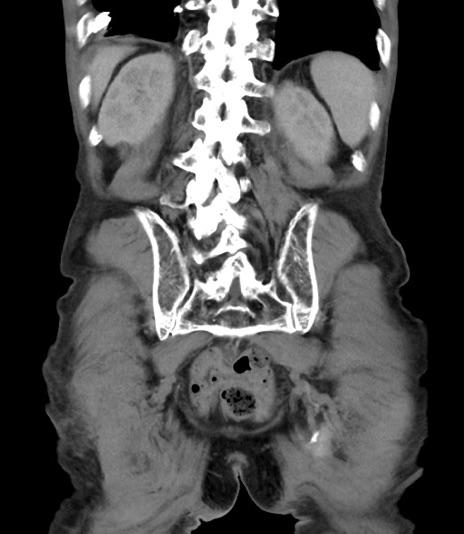

症例3(冠状断像)

【症例】 70歳代男性

【主訴】右鼠径部腫瘤、疼痛

【現病歴】本日朝より上記主訴あり、受診。

【既往歴】膀胱癌にて膀胱全摘、両側尿管皮膚瘻

【データ】WBC 5600、CRP 0.56

矢状断像